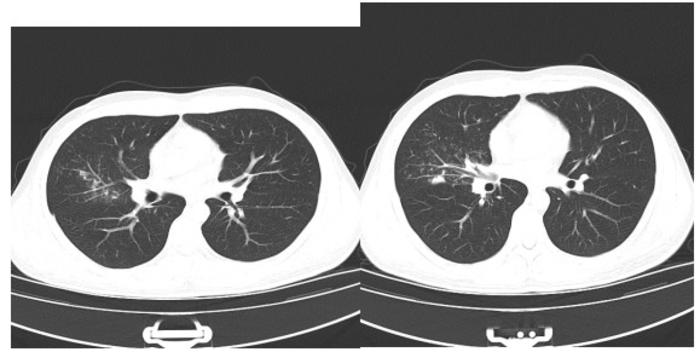

辅助检查:血常规:白细胞20.05×109/L;中性粒细胞77.3%;红细胞、血小板正常。胸部CT如下:

胸部CT未见明显异常,于是我们给他做了支气管镜检查,在患者左肺上叶支气管发现了支气管异物——鱼刺。

图6-7

支气管镜下发现异常后,我们再仔细回看做支气管镜检查前的胸部CT:

图8

可能有经验且细心的同道发现了该病灶,但如果这张图是放在没有任何提示的361张图片里,你确定还能发现病灶吗?当时影像科和临床医师都没有发现,如果我不做标识,相信非常多的人也看不出来。

图9